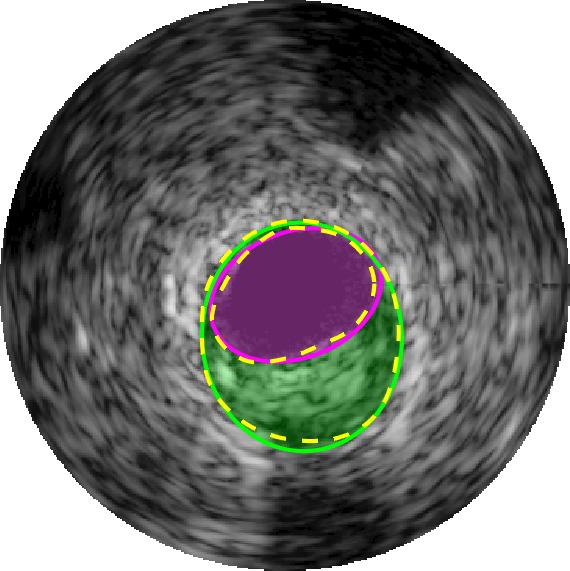

Qualitative evaluations are illustrated in Figure 4 and show the successful segmentation results of the proposed EREL selection strategy for 20 IVUS frames. The lumen areas are highlighted by the magenta colour while the media regions are green. Also, the manually annotated contours for both lumen and media are drawn as yellow dashed lines. As we can see, the chosen frames contain a variety of lumen and media morphologies.